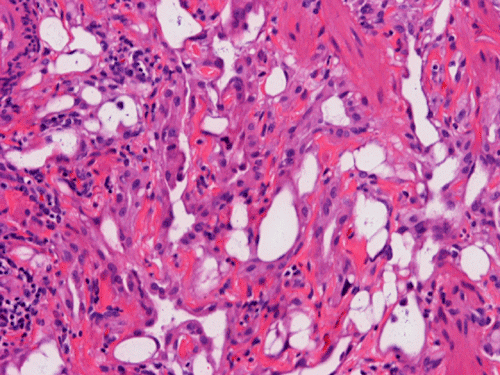

On scanning magnification, there is a round lesion in tissue around the fallopian tube (arrows in Panel A). The lesion does not invade into the tube nor distort or compress the tube. The cross sectional dimension is about the same diameter of the fallopian tube. On low and medium magnification, the lesion is composed of a collection of small microcysts intermingled with the smooth muscle bundles of the wall of the fallopian tube (Panel B and C). On higher magnification, the cyst or gland like spaces are lined by epithelioid to spindle cells with bland nuclei and an abundant amount of amphophilic cytoplasm (Panel D and E). The spindle cells are positive for calretinin, cytokeratin 5/6, and inhibin (Panel F, G, and H).

Histologically, the salient feature is small, microcystic or gland-like cystic spaces lined by flattened cells. Some of the tumor cells may arrange in cords and tubules.  Hyaluronic acid rich material that can be easily demonstrated by Alcian blue stain are present in the small glands and cysts. The tumor cells are medium in size and contain moderate to abundant amphophilic to eosinophilic cytoplasm. Prominent cytoplasmic vacuoles that suggest signet ring cells may be present. This is an important feature to know in order not to confuse these tumors with primary and metastatic carcinomas particularly when the specimen is obtained from the ovary. Although these tumor appears well-circumscribed on gross examination, these tumor appears infiltrative on microscopically and should not be confused with adenocarcinoma. The key to avoid this pitfall is that adenomatoid tumor have bland nuclear feature and no mitotic figures. Infaction can occur in adenomatoid tumor.